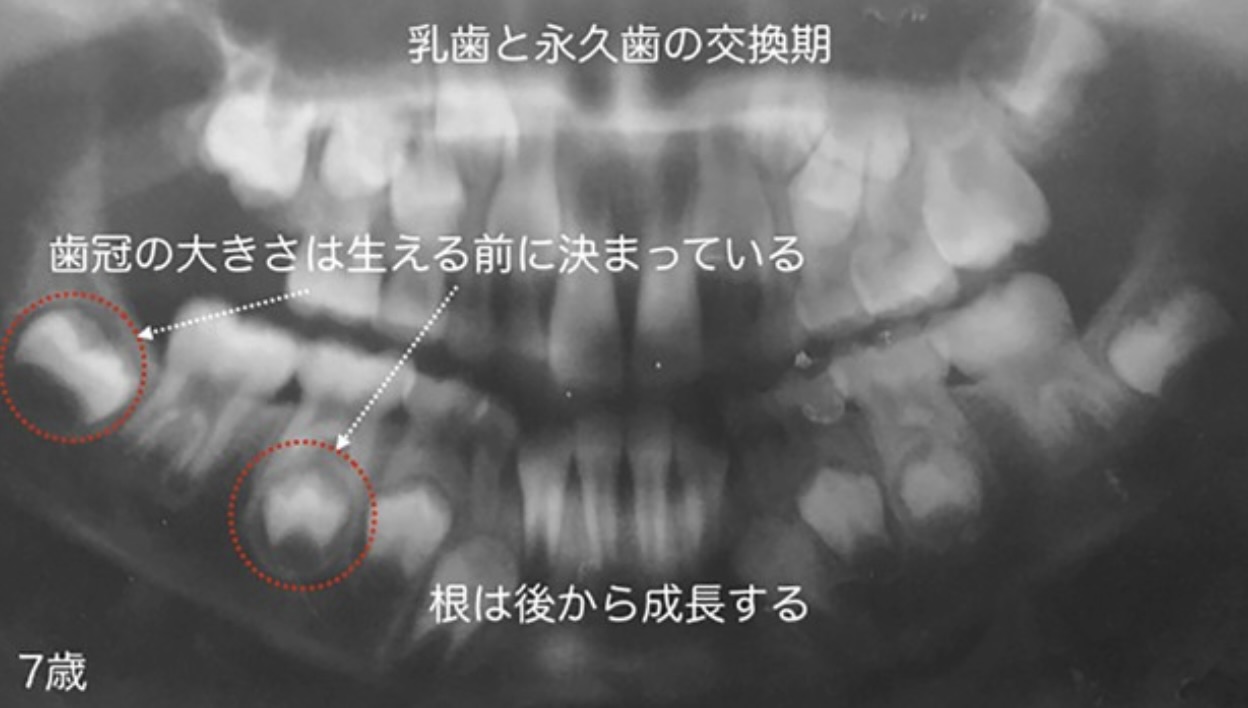

乳歯と永久歯の交換期

前号で成長期の子どもの咀嚼(そしゃく)が咬合(こうごう)力(噛(か)む力)や記憶力に大きな影響を与えることを解説しました。能力だけでなく、永久歯の歯並びも乳幼児からの咀嚼が影響します。

子どもの虫歯は減少していますが、叢生(そうせい)(乱ぐい歯)のある子どもは増えています。叢生とは「歯の大きさと顎(あご)の大きさの間に起こるアンバランスにより、歯が部分的に重なってしまう状態」(厚生労働省 e-ヘルスネット)のことです。臼歯(きゅうし)が重なり合うことは非常にまれで、主に前歯の歯並びが乱れます。12~15歳で叢生のある人は34.5%(2005年)から43.8%(11年)と増加傾向です(歯科疾患実態調査/厚労省)。叢生の原因と考えられるのが、乳幼児期からの咀嚼不足です。

乳歯も永久歯もその大きさは生える前から決まっています。永久歯に生え変わる時期に顎が十分発育していないと、大きさの決まっている歯が顎に収まりきらず、ねじれたり、重なり合ったりして歯並びが乱れてしまうのです。…【続きを Amazon で読む】